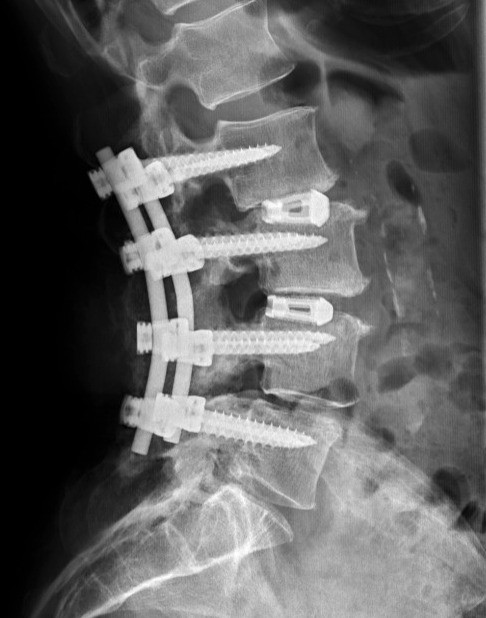

XLIF: Minimally Invasive Lateral Spine Fusion Surgery